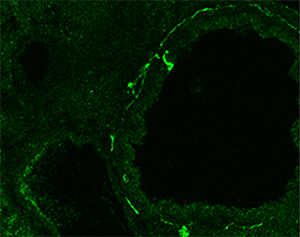

Project IV: Nerve and childhood asthma

Allergic asthma often initiates from allergen exposure in early childhood and progresses into adulthood. As the lung continues to develop after birth, this project investigates age-related communication between the immature lung environment and the immune system in the pathogenesis of allergic asthma. So far, our findings have pinpointed a novel role of developing sympathetic nerves in augmenting allergic inflammation in early childhood and fostering disease progression into adulthood. We also show that immune cells, such as mast cells, can also modulate airway innervation during postnatal development, which induces a hypercontractile phenotype of airway smooth muscle cells. By understanding the age-related mechanism underlying the development of allergic asthma in early childhood, our goal is to identify novel therapeutic targets for the treatment of childhood asthma and the modification of disease progression in adulthood.